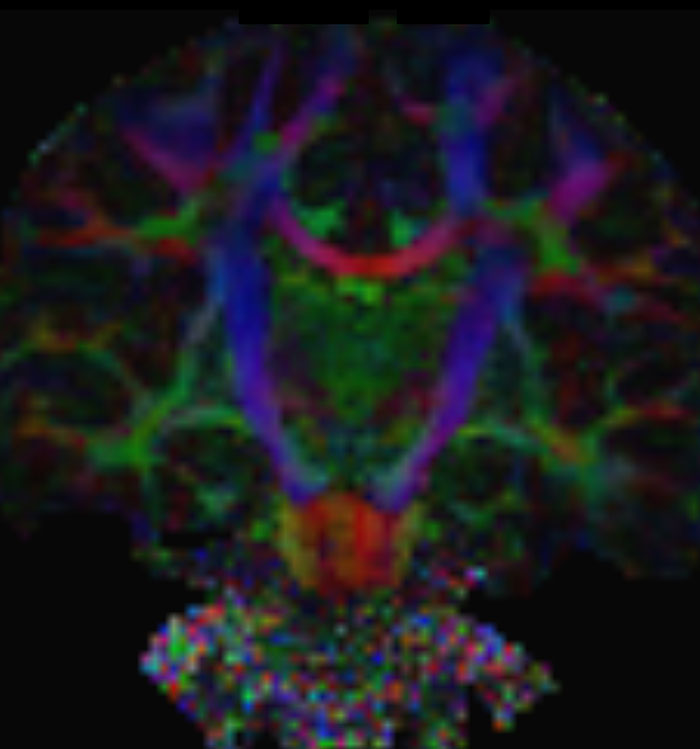

Resting state fMRI

Imaging was performed using Ingenia 3T CX with a 32ch dS Head coil, TR 1.6 sec, TE 35 ms, voxel size 3.1 x 3.1 x 3.1 mm, 46 slices and Multiband SENSE factor 2. Image provided by Dr. Gispert

Default mode network as discovered by resting state fMRI in one participant of the ALFA cohort [7]. rs-fMRI allows us to find networks of brain regions with highly correlated activity and sustaining distinct brain functions. The default mode network (in warm color scale) is active when the brain is focused on introspective thinking and has been shown to be altered in Alzheimer’s. Interestingly, brain areas of this network are known to show abnormal levels of one of the pathological hallmarks of Alzheimer’s (b-amyloid deposition) in preclinical stages. We want to better understand the alterations of these brain networks in preclinical stages of Alzheimer's and explore their potential use as biomarkers.